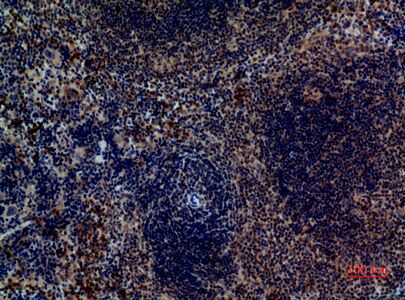

Immunohistochemical analysis of paraffin-embedded mouse-spleen, antibody was diluted at 1:100